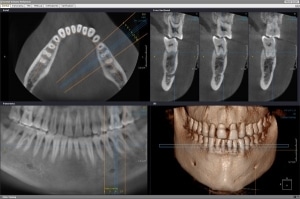

At Brookside Dental Centre, we use Cone Beam Computed Tomography (CBCT) to provide highly detailed 3D images of your teeth, jawbone, and surrounding dental structures. This advanced imaging technology helps our team plan treatments with precision and accuracy.

CBCT scans are especially valuable in implant dentistry, orthodontic planning, and endodontic treatments (such as root canals). The scan captures a complete view of the mouth and jaw in a single rotation, giving us a clear understanding of bone structure, tooth position, and nerve pathways before any procedure begins.

CBCT technology has transformed modern dentistry by moving from 2D to 3D imaging, allowing for safer, more predictable, and customized dental care.